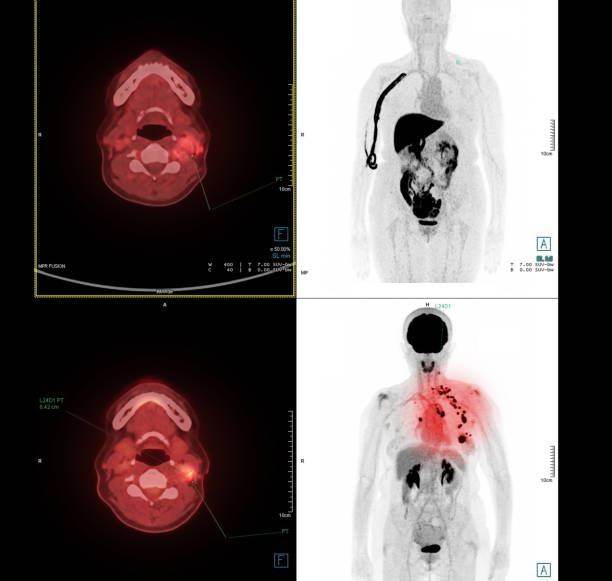

肺癌

慢性阻塞性肺病 (COPD) 是肺癌的一個(gè)獨(dú)立危險(xiǎn)因素,這意味著即使你從未吸煙,它也會(huì)增加你的患癌風(fēng)險(xiǎn)。當(dāng)然 ,如果你確實(shí)吸煙,戒煙可以幫助降低吸煙習(xí)慣帶來的額外風(fēng)險(xiǎn)。